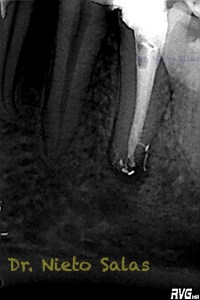

Es muy importante cambiar la proyección de las Rx para tener más información de como hemos sellado el sistema de conductos.

Como sabrás, son muchas las piezas dentarias que presentan conductos laterales, lo primero, es descartar que la imagen pueda ser una fractura vertical, después conformo el sistema de conductos, y si sospecho de un conducto lateral ( INTUICIÓN ) precurvo una lima de pequeño diámetro y exploro las paredes en la zona de puede estar. En ocasiones, puedes ver un pequeño puntito, la entrada, con el microscopio. (es raro).